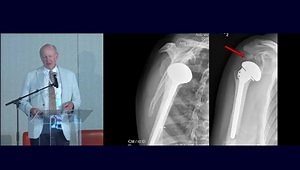

Distal Humerus Fractures - Eric Bl…